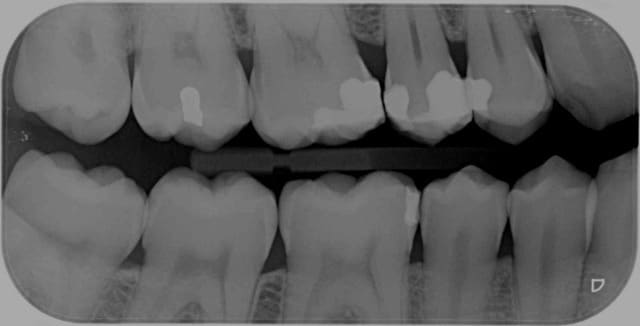

Que peut on coter comme radios dans ce cas ?

Capteurs trop petits pour prendre la crête alvéolaire antagoniste !

Et la solution?

Un capteur numérique plus grand?

Qu'aurait-il fallu à ces radios ?

Les film ERLM 3+ DurrDental... ils permettent de réaliser des rétro-coronaires opposables. (voir cliché trouvé sur ce forum)

la solution c'est ca :

4 rétro coronaires. -)

Rien a dire couronnes et crêtes alvéolaires visibles sur 4 secteurs. Qui peut le plus peut le moins. -)

" quel que soit le nombre de clichés" je le rappelle. -)

Tu n'as pas 2 secteurs en rétro-coronaires mec. il te manque les couronnes des canines. -)